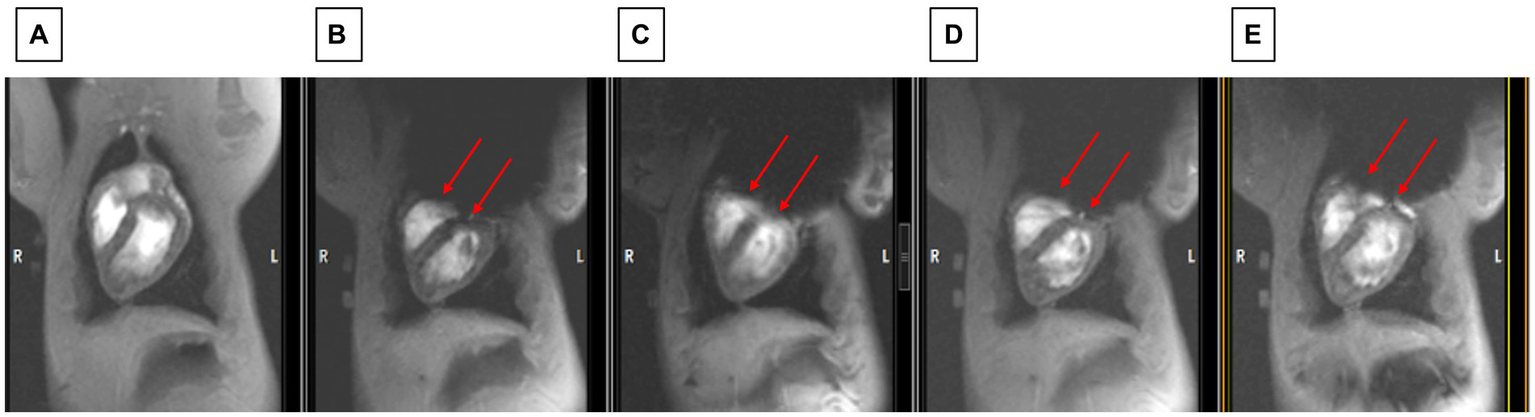

Another sequence that permitted rapidly observing improvement in shimming in the swine was execution of 2D ECG-gated multiphase GRE scans during the repositioning of the shim coil location. Figure 8 shows how improved positioning can provide an LV image similar to the baseline state (with no ICD above the chest), which is shown in Figure 8A.

Figure 8

Observing changes during changes in shim coil positioning with cine imaging. (A) The state before the ICD was added (which serves as the baseline for restored image quality). (B) Worst post-ICD state, (C) slightly improved post-ICD state, (D) increasingly improved post-ICD state, (E) most improved post-ICD state. Note that LV visualization in E is almost as good as in A. Red arrows point to inferior border of void which is continuously moved between B and E.